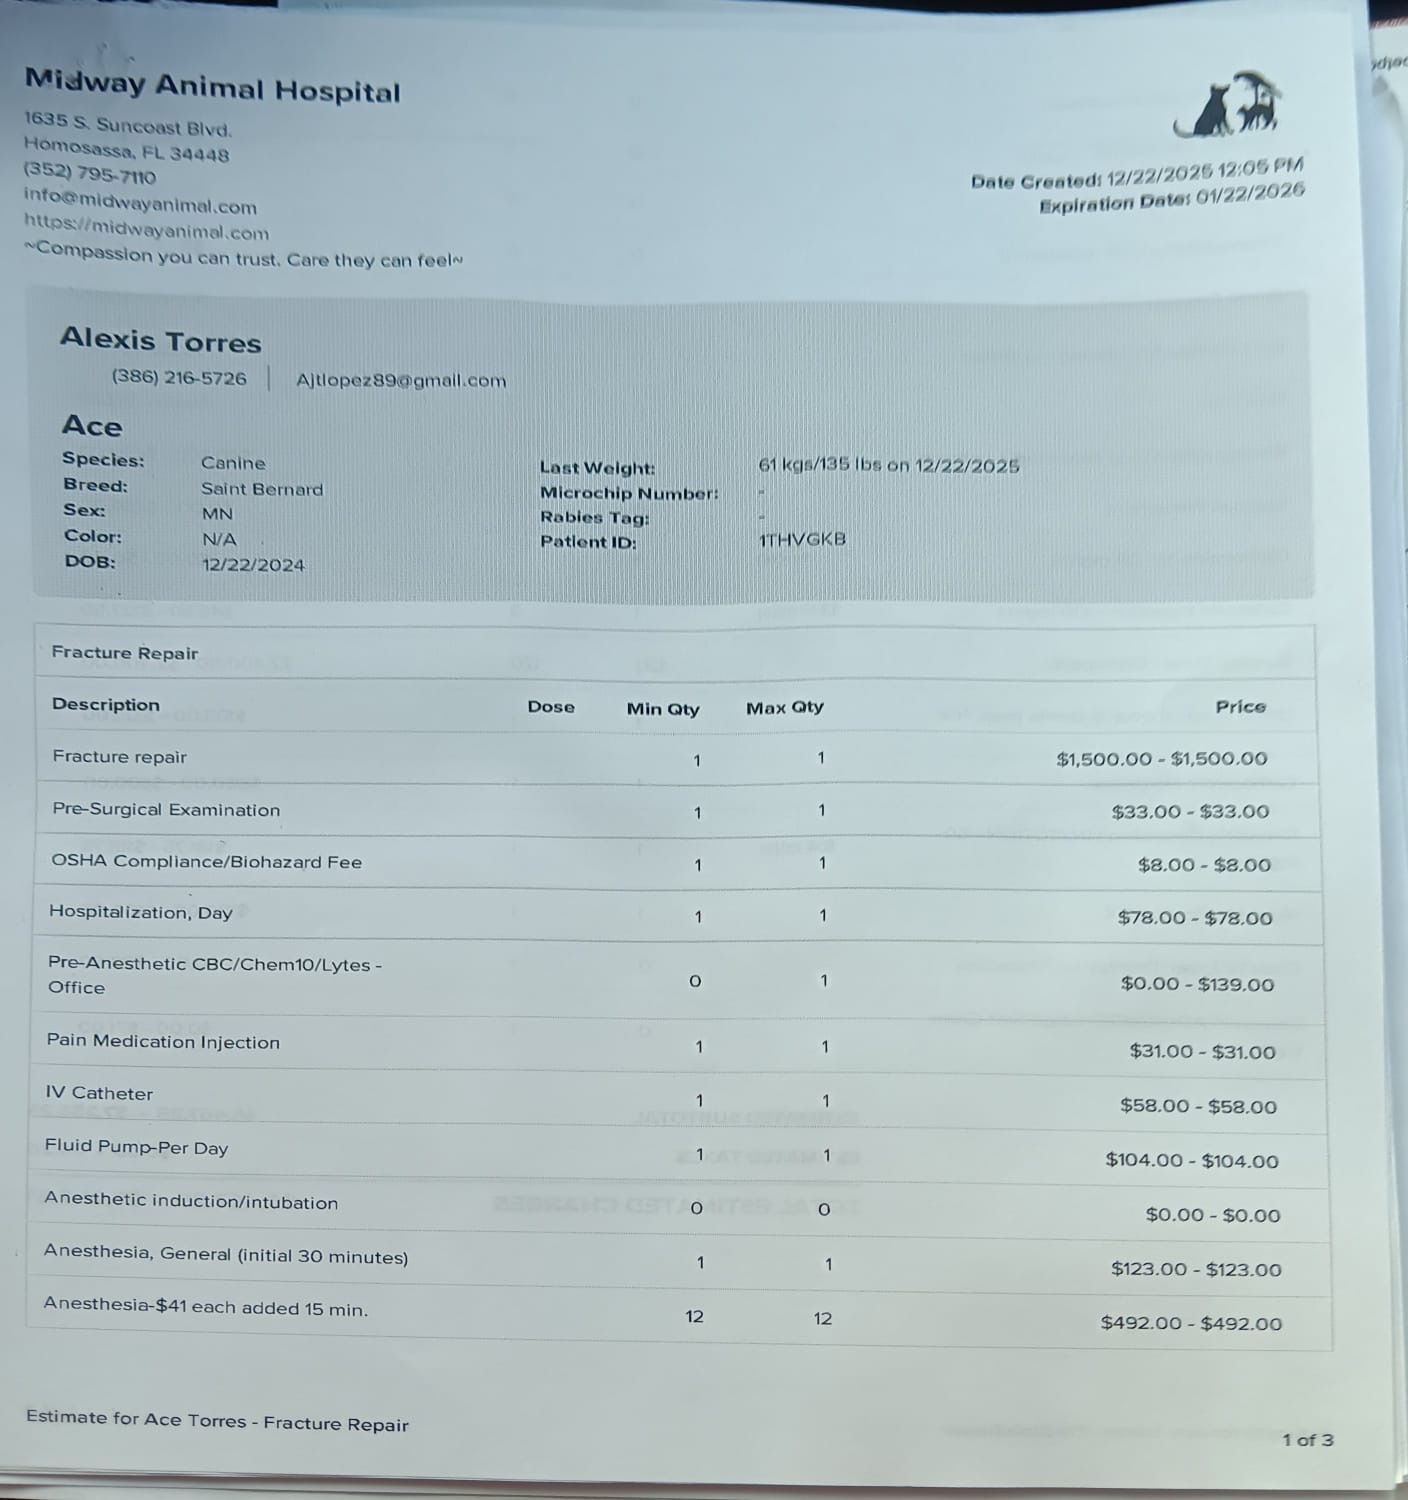

The funds raised will go directly toward Ace’s surgery and the medical care he needs to recover. This support will help cover the costs of his operation, medications, and follow-up treatments, giving Ace the best possible chance to heal and return to the happy, loving life he shares with us. We are doing everything we can, but we can’t do it alone.